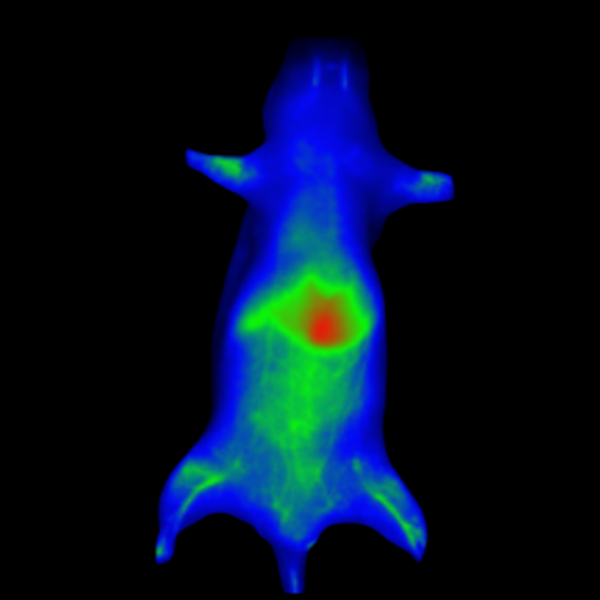

Bioluminescence imaging

Luciferase-expressing or secreting molecules in the target tissue can be found via bioluminescence imaging.

Subcutaneous tumor expressing firefly luciferase. Image Credit: Scintica Instrumentation Inc